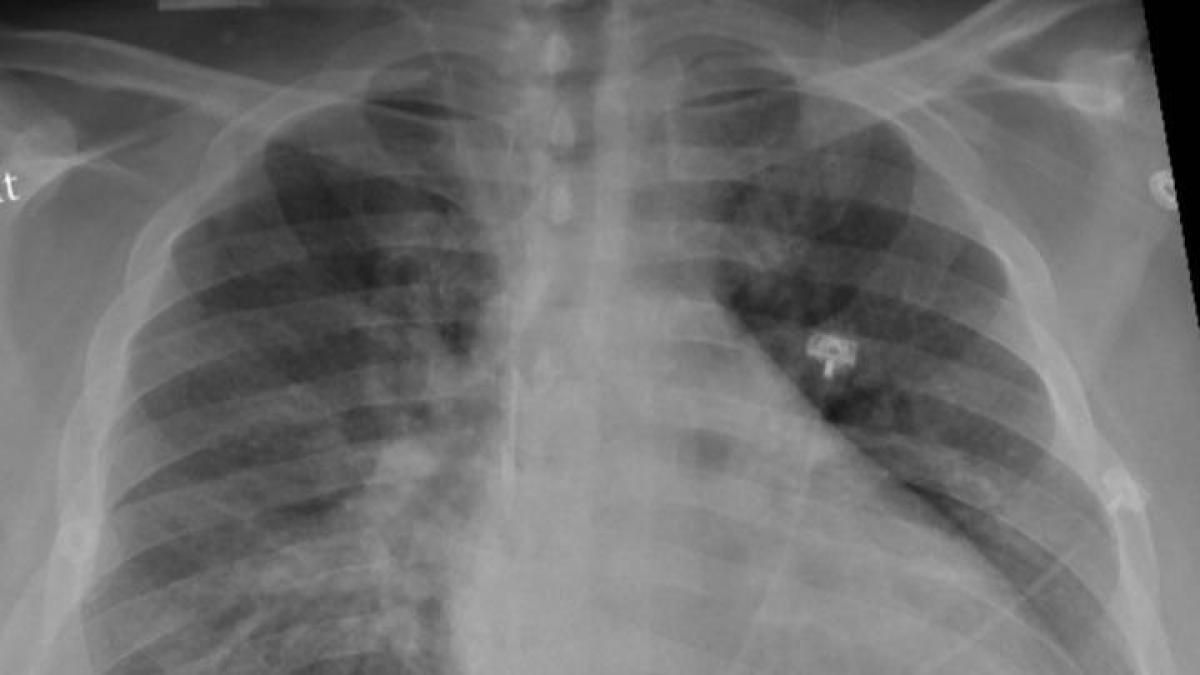

Un estudio multicéntrico promovido y coordinado por neumólogos del Hospital Clínico San Carlos de Madrid ha revelado que en pacientes diagnosticados de COVID-19 y déficit de alfa-1 antitripsina (enfermedad congénita que puede llegar a provocar enfisema pulmonar) la infección por SARS-CoV-2 aumenta la gravedad y mortalidad.

El déficit de alfa-1 antitripsina es una condición genética que aumenta los riesgos de sufrir enfermedades respiratorias y hepáticas, y se genera porque el organismo no produce la suficiente cantidad de esta proteína, que protege al pulmón de las agresiones provocadas por agentes externos como el tabaco u otras sustancias inhaladas que son contaminantes e irritantes.

Se trata de una enfermedad congénita que tiene una prevalencia más alta que la hipertensión pulmonar o la fibrosis quística, que afecta también a pacientes con EPOC, y que puede provocar el desarrollo de enfisema pulmonar y enfermedad hepática.